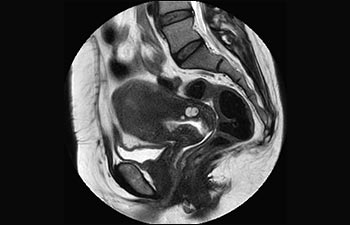

La Sra. Silvia Schiffer, directora y radióloga experta en la clínica Radiologie Schiffer, en Alemania, comparte sus experiencias con el sistema de RM Prodiva 1.5T.

Conozca la opinión de los primeros usuarios de Ingenia Prodiva 1.5T acerca de sus experiencias con el sistema y cómo influye este en su centro de diagnóstico por imagen.